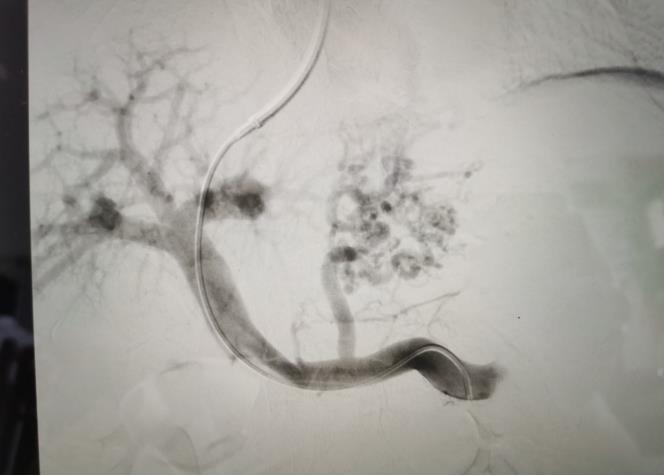

血管介入科通訊員吳超報道:2022年1021日,血管介入科成功為一位肝硬化門靜脈高壓消化道出血患者實施經(jīng)頸靜脈門體靜脈分流(TIPS)手術(shù)。

經(jīng)過我院血管介入科醫(yī)療團隊的精心準備,患者在數(shù)字減影血管造影機(DSA)導(dǎo)引下,順利經(jīng)頸靜脈入路進入下腔靜脈并成功穿刺了門靜脈右支主干,術(shù)中栓塞了曲張的胃冠狀靜脈-食管靜脈叢將支架植入肝實質(zhì)內(nèi),支架兩端分別置于門靜脈和肝靜脈內(nèi),術(shù)程歷時2小時,術(shù)中患者時刻保持清醒,手術(shù)切口僅5毫米,術(shù)后第2天恢復(fù)飲食,腹脹、腹水癥狀明顯好轉(zhuǎn),未出現(xiàn)嘔血、黑便及肝性腦病等并發(fā)癥,術(shù)后第3天康復(fù)出院